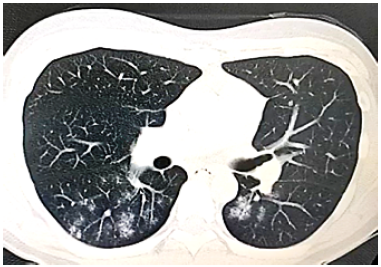

Figure 2 shows the result of the non-contrast chest CT scan performed on the patient, where ground-glass opacities associated with interstitial thickening of patchy distribution were found predominantly in the posterior basal segment of both lung fields. This was consistent with viral atypical pneumonia and confirmed the presence of COVID-19.

Non-contrast chest CT scan showing lesions consistent with COVID-19 atypical pneumonia.

Figure 2: Non-contrast chest CT scan showing lesions consistent with COVID-19 atypical pneumonia.

Source: Document obtained during the study.